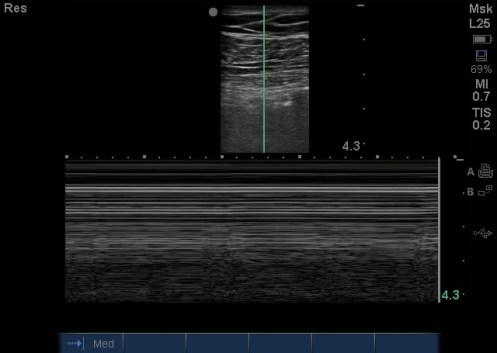

That left side had no lung sliding and a stratosphere sign on M Mode, that’s the first thing that Dr. Chough appreciated, but it was also unclear as to why it was so echogenic (gray) beneath the pleural line. He had no signs of tension pneumothorax on clinical exam, so instead of performing a needle thoracostomy and chest tube, she aborted the rest of the RUSH and ordered a stat Chest XR: